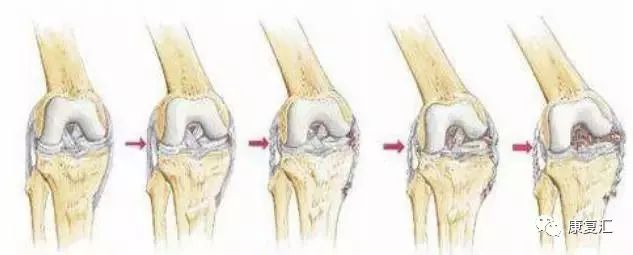

剥脱性骨软骨炎

关节内的骨软骨病,病因不明,关节软骨和软骨下骨变性和再钙化,最常见于股骨内髁,模糊的、定位不清的膝关节疼痛,有晨僵,反复的关节内积液(轻度)。如有游离体,可发生交锁症状。股四头肌萎缩,受累股骨髁关节软骨面压痛。

X线平片显示骨软骨病损或关节内游离体。如怀疑剥脱性骨软骨炎,摄片应包括前后位、后前隧道位、侧位和髌股关节切线位。